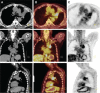

Objective: Lung cancer is the most common cause of cancer-related death throughout the world, and the correct choice of treatment based on early diagnosis and staging increases the chance of survival. The present study aims to investigate the contribution of fluorine 18-fluorodeoxyglucose-positron emission tomography/computed tomography (18F-FDG PET/CT) to the management of lung cancer.

Methods: In this study, 50 patients who underwent 18F-FDG PET/CT for lung cancer diagnosis and staging between February 2012 and February 2014 were included. The maximum standardized uptake value (SUVmax) of the primary lung lesion along with other findings of 18F-FDG PET/CT and the results of histopathologic and conventional examinations were evaluated retrospectively. The mean survival time of patients was determined, and the findings were compared by using statistical methods.

Results: Histopathologic examinations revealed 51 lung cancers in 50 patients. The sensitivity, accuracy and positive predictive value of 18F-FDG PET/CT in detecting primary malignancy were 94%, 94%, 100%, respectively. Adenocarcinoma (n=23, 16.8±13.5) and squamous cell carcinoma (n=15, 17.9±5.6) did not differ significantly regarding their mean SUVmax values (p=0.2). A statistically significant positive correlation (r=0.4) was identified between tumor size and SUVmax value for 51 tumors (p=0.002). The 18F-FDG PET/CT result was true negative in nine, false positive in six, true positive in two, and false negative in four patients who underwent histopathologic evaluation of their lymph nodes. The 18F-FDG PET/CT changed treatment planning in 34% of the patients. No significant relationship was identified between SUVmax value of the tumor and patient survival in patients (p=0.118).

Conclusion: The present study concluded that PET/CT was an efficient method in the diagnosis and staging of lung cancer since it provided useful information in addition to conventional methods. It was also observed that PET/CT scanning resulted in a change in therapeutic plans in the majority of patients. However, there was no statistically significant relationship between survival and the SUVmax of the primary mass.